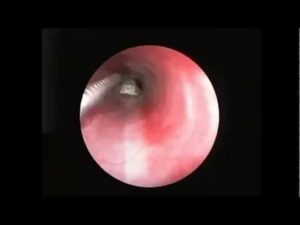

Если человек не может самостоятельно вытащить рыбью кость, ЛОР-врач может легко ее удалить. Если он не видит рыбью кость в задней части горла, он, скорее всего, проведет эндоскопию. Эндоскоп — это длинная гибкая трубка с маленькой камерой на конце. Также врач может использовать этот инструмент, чтобы извлечь рыбную кость или протолкнуть ее вниз в живот.

В большинстве случаев бывает сложно определить место локализации кости. Если она застряла между ротоглоткой и гортаноглоткой, то возникают не локальные, а разлитые болевые ощущения. Чтобы обнаружить кость в пищеводе, необходимо провести эндоскопическое исследование.